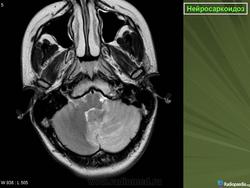

ID: 17921 Neurosarcoidosis Dr Frank Gaillard - 25 May 2012 The case demonstrates typical features of neurosarcoidosis, which are of...

Случай 1: с участием лептоменинга

Случай 2: с участием паренхимы

Случай 3

Случай 4: вокруг гипофизарного стебля

Случай 5: вовлечение спинного мозга

Случай 6: вовлечение гипофизарного стебля

Рисунок 8

Рисунок 8 Нейросаркоидоз.